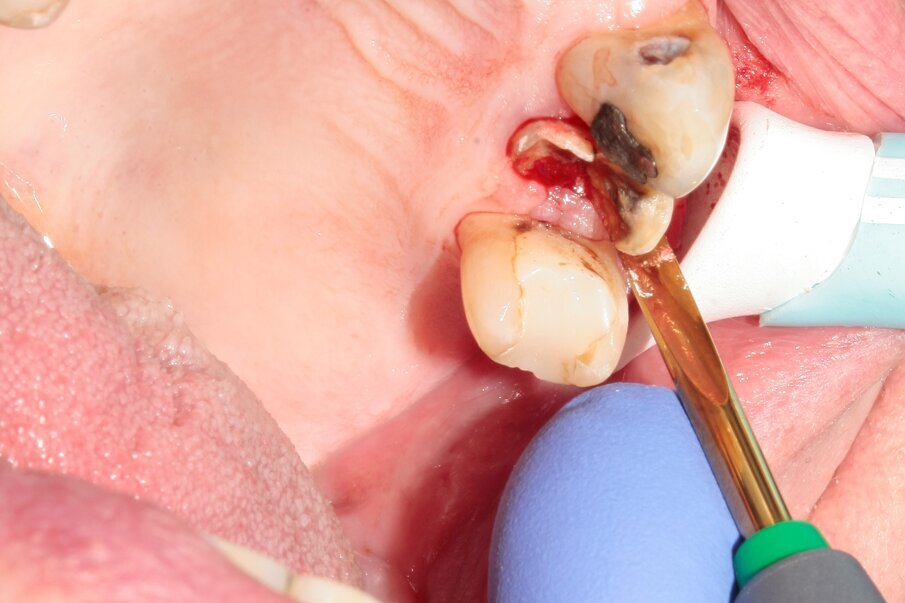

Figs. 5–7: Luxation was continued with Luxator P1 (straight blade, dark green).

Fig. 8: The tooth was removed with the help of diamond tweezers.